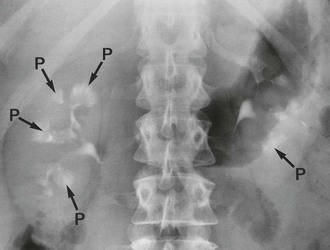

(a) A 48-year-old woman with recurrent urinary tract infections; IVU shows abnormal pelvicalyceal systems P of bilateral pelvic kidneys.